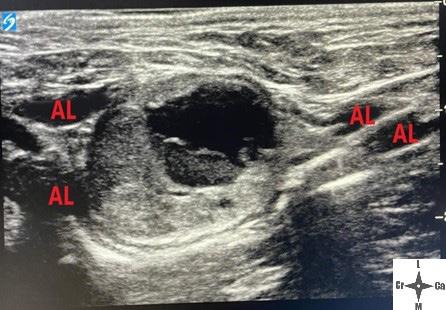

Diagnóstico por imagen Los hallazgos no son específicos de pacientes infecta dos con parvovirus. Las radiografías abdominales pue den ser normales al inicio de la enfermedad, o mostrar signos de íleo con distensión de asas intestinales por acúmulo de líquido o gas. Los signos ecográficos son asimismo inespecíficos, mostrando áreas de distensión con fluido y gas tanto en estómago como en intestino, íleo con movimientos peristálticos inefectivos, efusión peritoneal anecoica, etc.1,2,5,6 Ambas técnicas ayudan a descartar otras causas del cuadro clínico, como son cuer pos extraños, obstrucción e invaginación intestinal.1,2,5,6